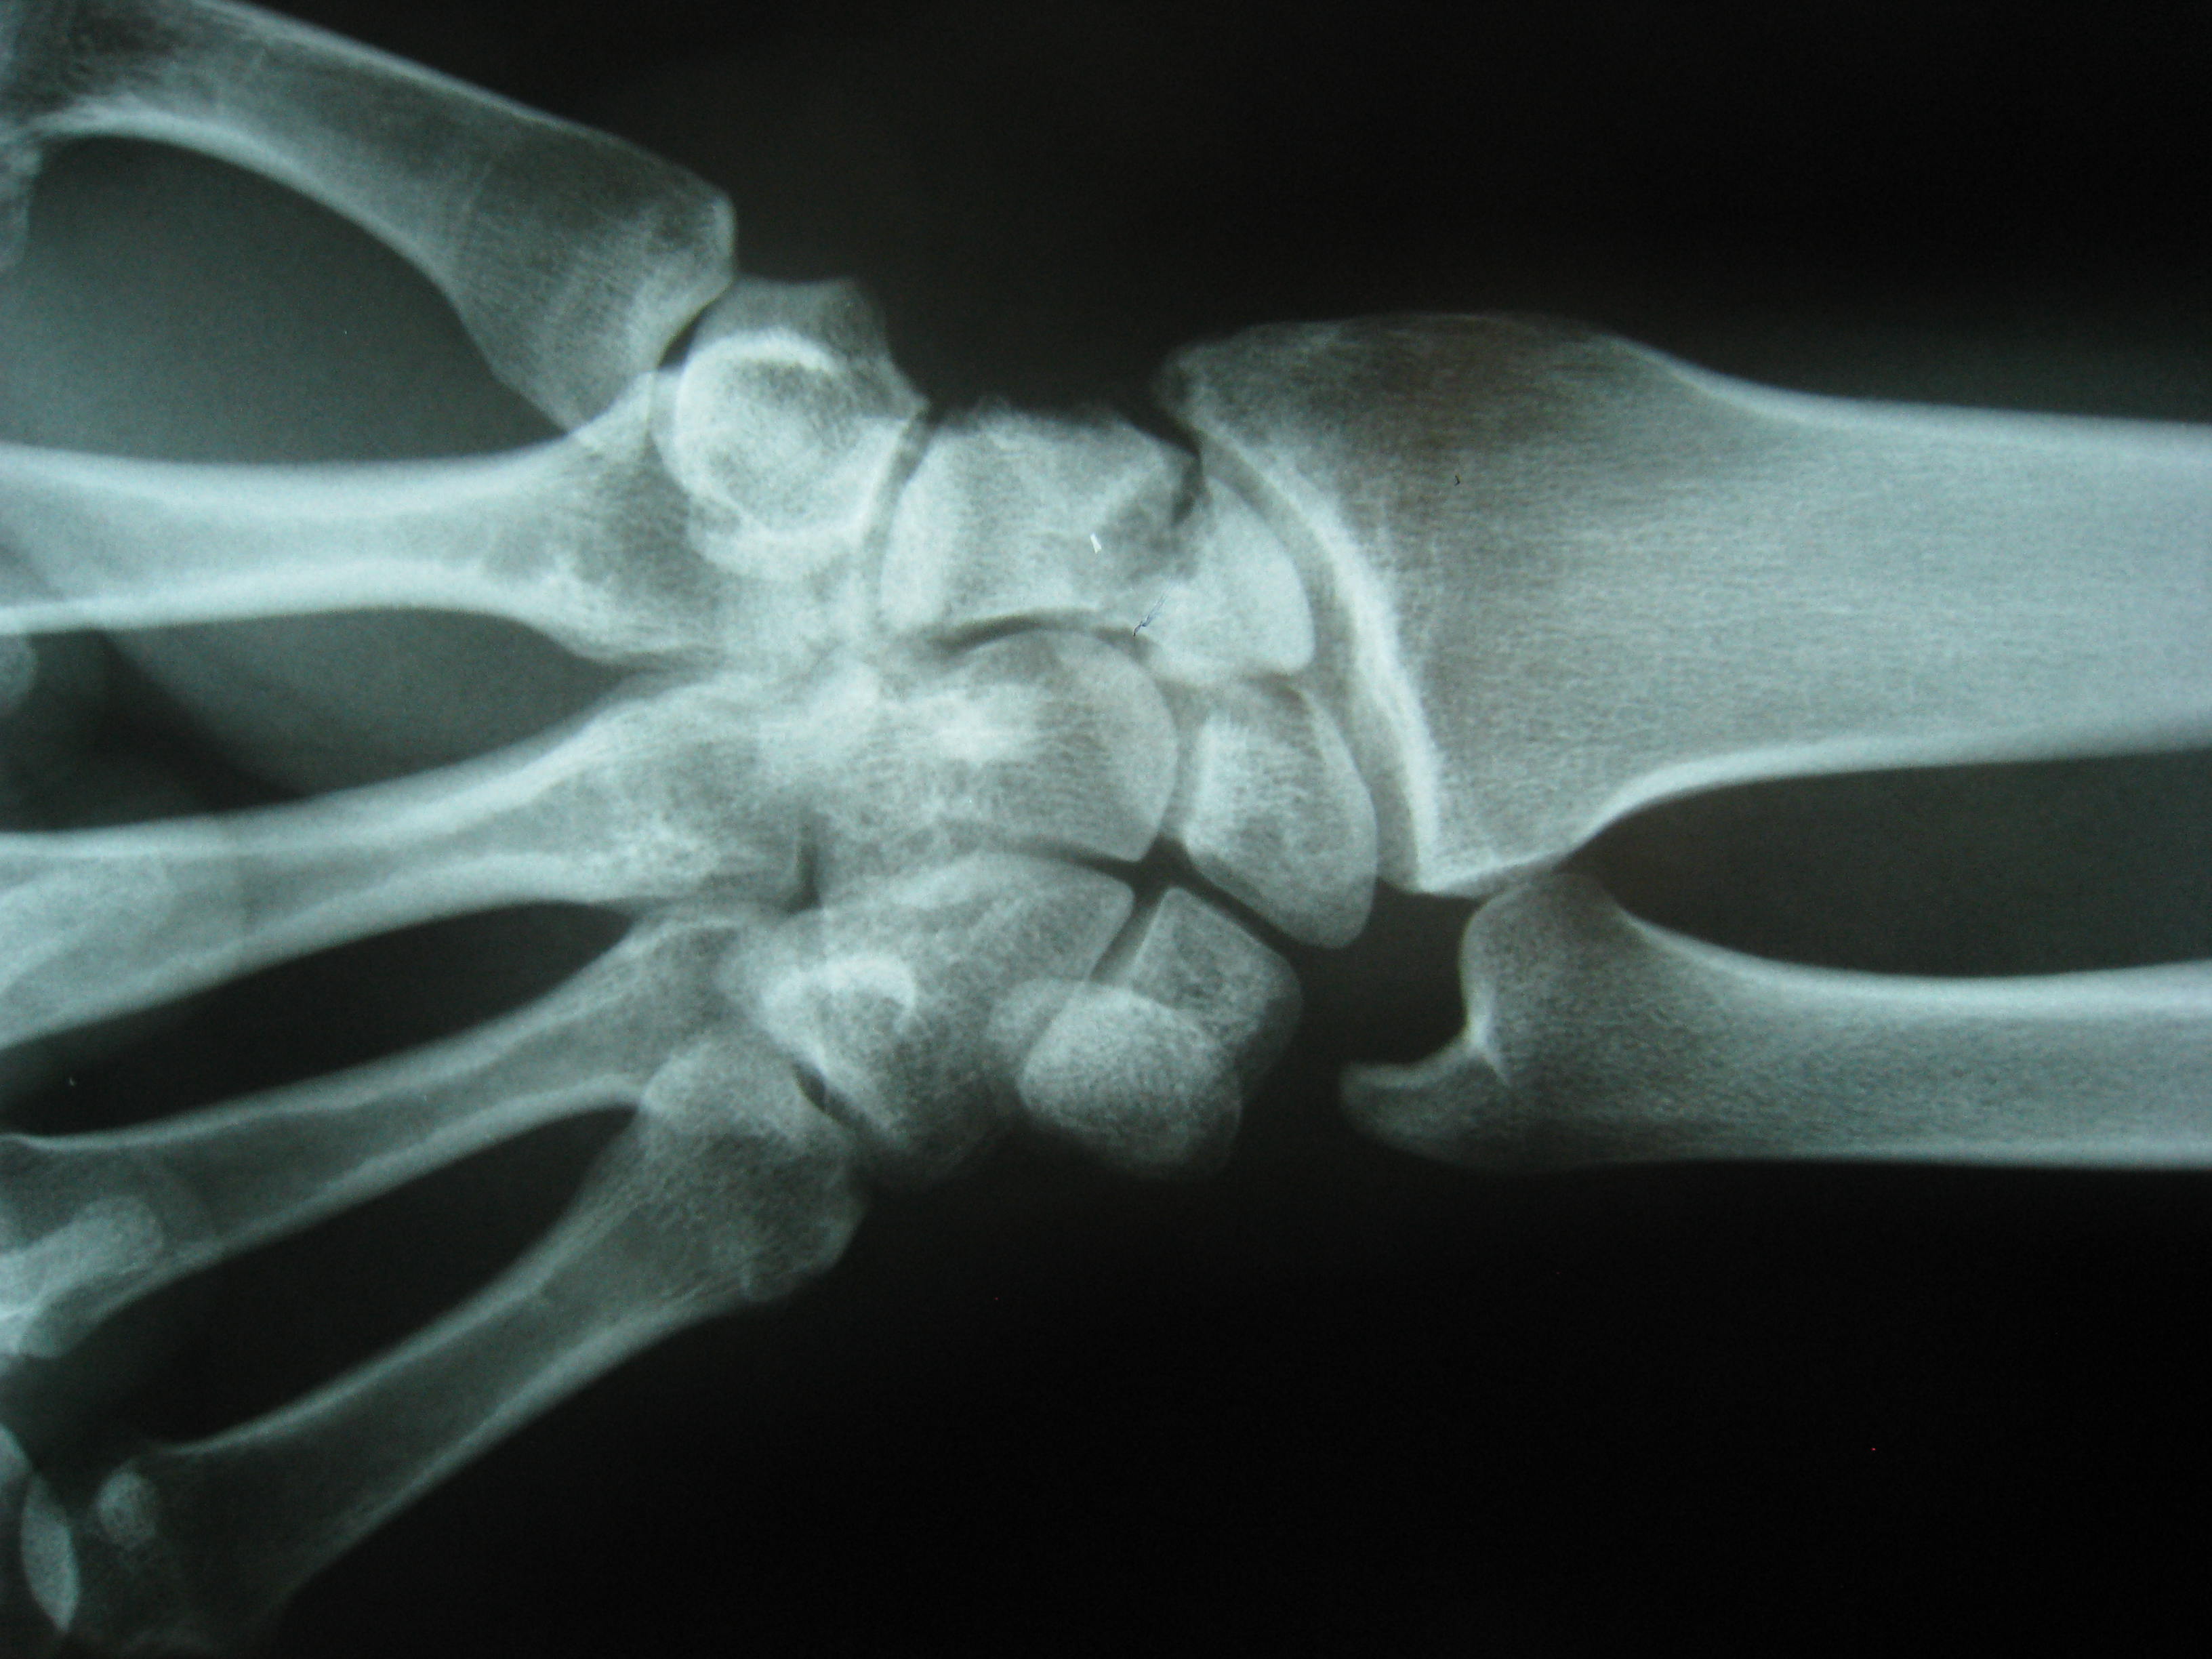

Προεγχειρητικά

Περίπτωση 2: Προεγχειρητικά